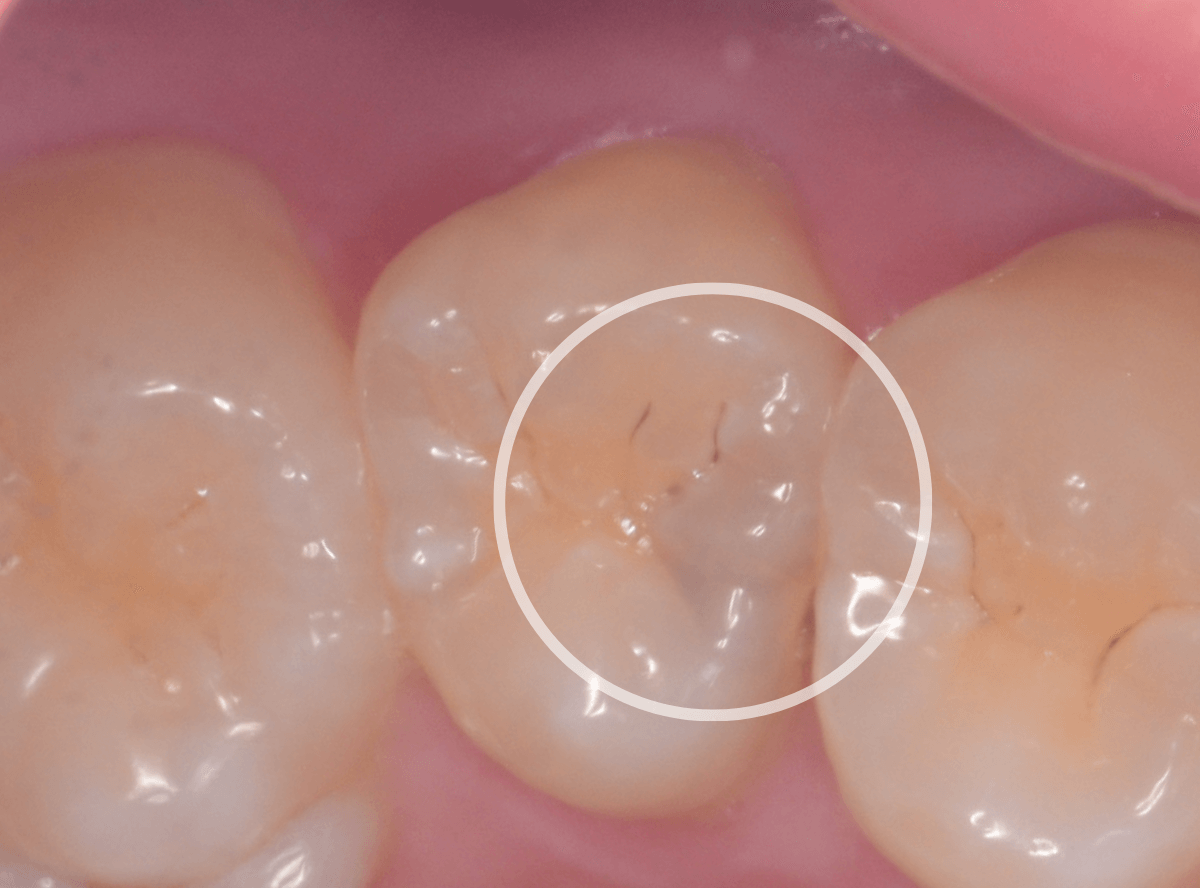

Case.7 レントゲンに写らないレジンの中の虫歯を削って調べる

こちらも定期検診希望で来院された患者さんです。

特に症状はありませんが、歯の咬頭(噛み合わせの山の部分)に小さな穴が空いていて、その周りがもやっと黒く見え、虫歯が怪しいです。

レントゲン写真で確認しますが、ここでは特に問題はなさそうに見えます。

患者さんに状況を説明し、慎重に削って調べる事になりました。

少しずつ穴の部分を削ってみると、ズブッと落とし穴にはまるような柔らかい虫歯の層(=軟化象牙質)に当たりました。

慎重に虫歯を除去したところです。

歯の溝のレジンが詰めてあった部分まで虫歯は進行していました。

とはいえ、それほど深く虫歯は進行していませんでしたので、虫歯除去後、レジンを充填して治療は終われました。

このように定期的にメンテナンスに来ていただくと虫歯が本格的に進行する前に対処する事ができます。